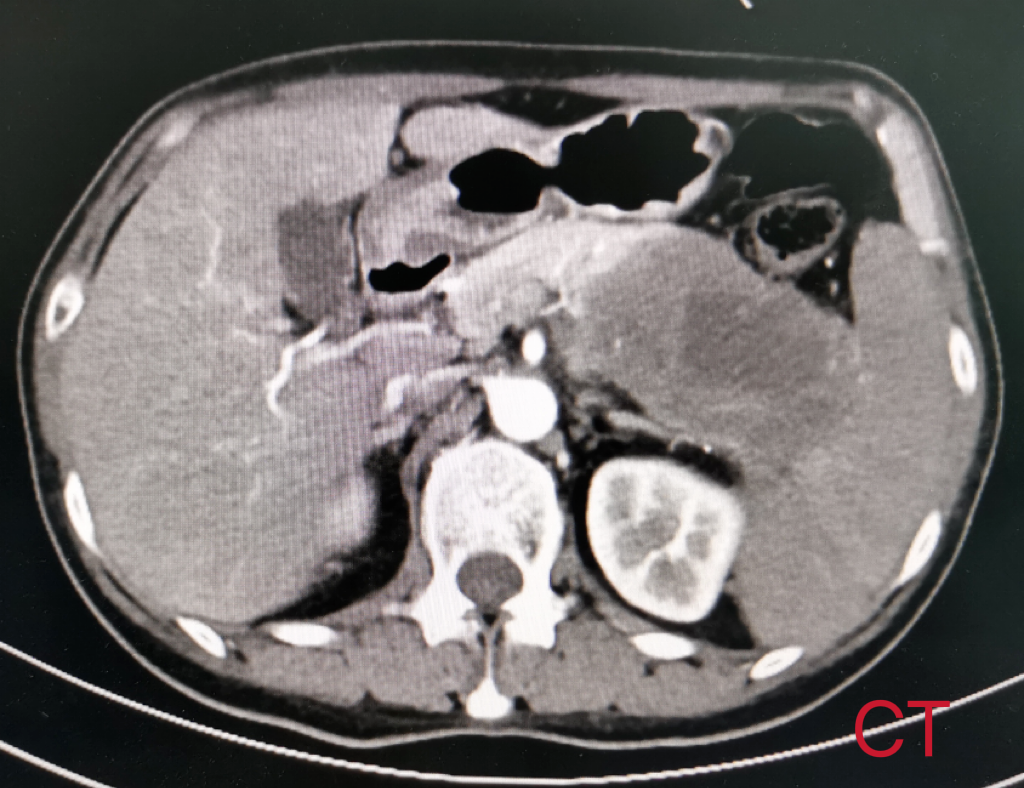

患者女性,57岁,因“间断左上腹疼痛3月余”入院,既往无特殊疾病史。入院后完善相关检查提示:胰腺尾部占位性病变,约8cm×5cm,考虑囊腺癌,累及脾动静脉和腹腔干可能性大。肠镜发现结肠距肛门30cm可见一肿物。患者腹痛逐渐加重,通过术前充分评估和讨论,祁向军主任认为结肠肿物为胰腺肿瘤侵犯所致,在与患者及患者家属充分沟通后,决定立即为患者施行手术治疗。考虑血管侵犯可能以及肿瘤较大,决定为其行胰体尾+脾根治性扩大切除术,包括胰体尾、脾、部分受侵结肠的切除以及周围腹腔淋巴结的清扫,并且备术中腹腔干的切断以及置换。手术成功完成,患者胰体尾、脾、和部分结肠完整切除,现患者已康复出院。